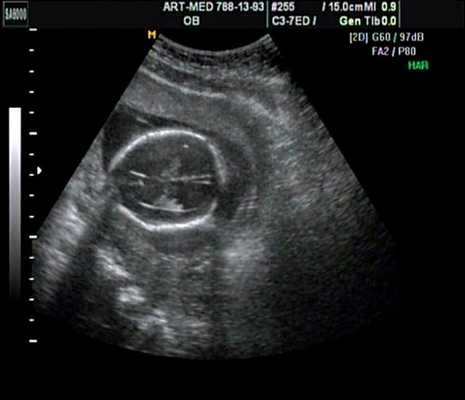

В прошлом лечащие врачи и врачи ультразвуковой диагностики проводили ультразвуковой скрининг для выявления дефектов нервной трубки, главным образом открытого расщепления позвоночника (spina bifida), во II триместре. В последние годы предложены ранние ультразвуковые маркеры на 11-14-й неделе беременности (внутричерепное пространство, использование БПР и соотношения БПР/ПРЖ (поперечный размер живота)), которые позволяют выявить у некоторых плодов высокий риск открытого расщепления позвоночника (рис. 7) 11.

Рис. 7. Внутричерепное пространство при ультразвуковом скрининге по поводу открытого расщепления позвоночника.